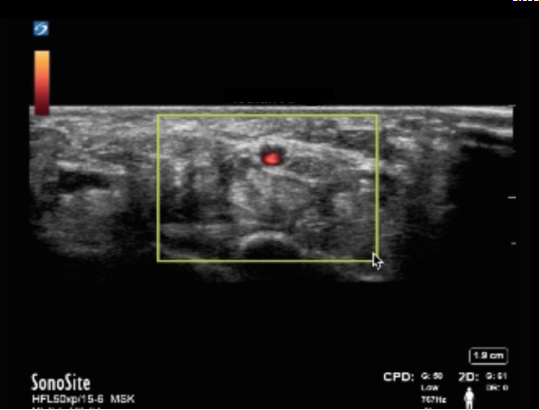

Wrist Persistent Median Artery Image